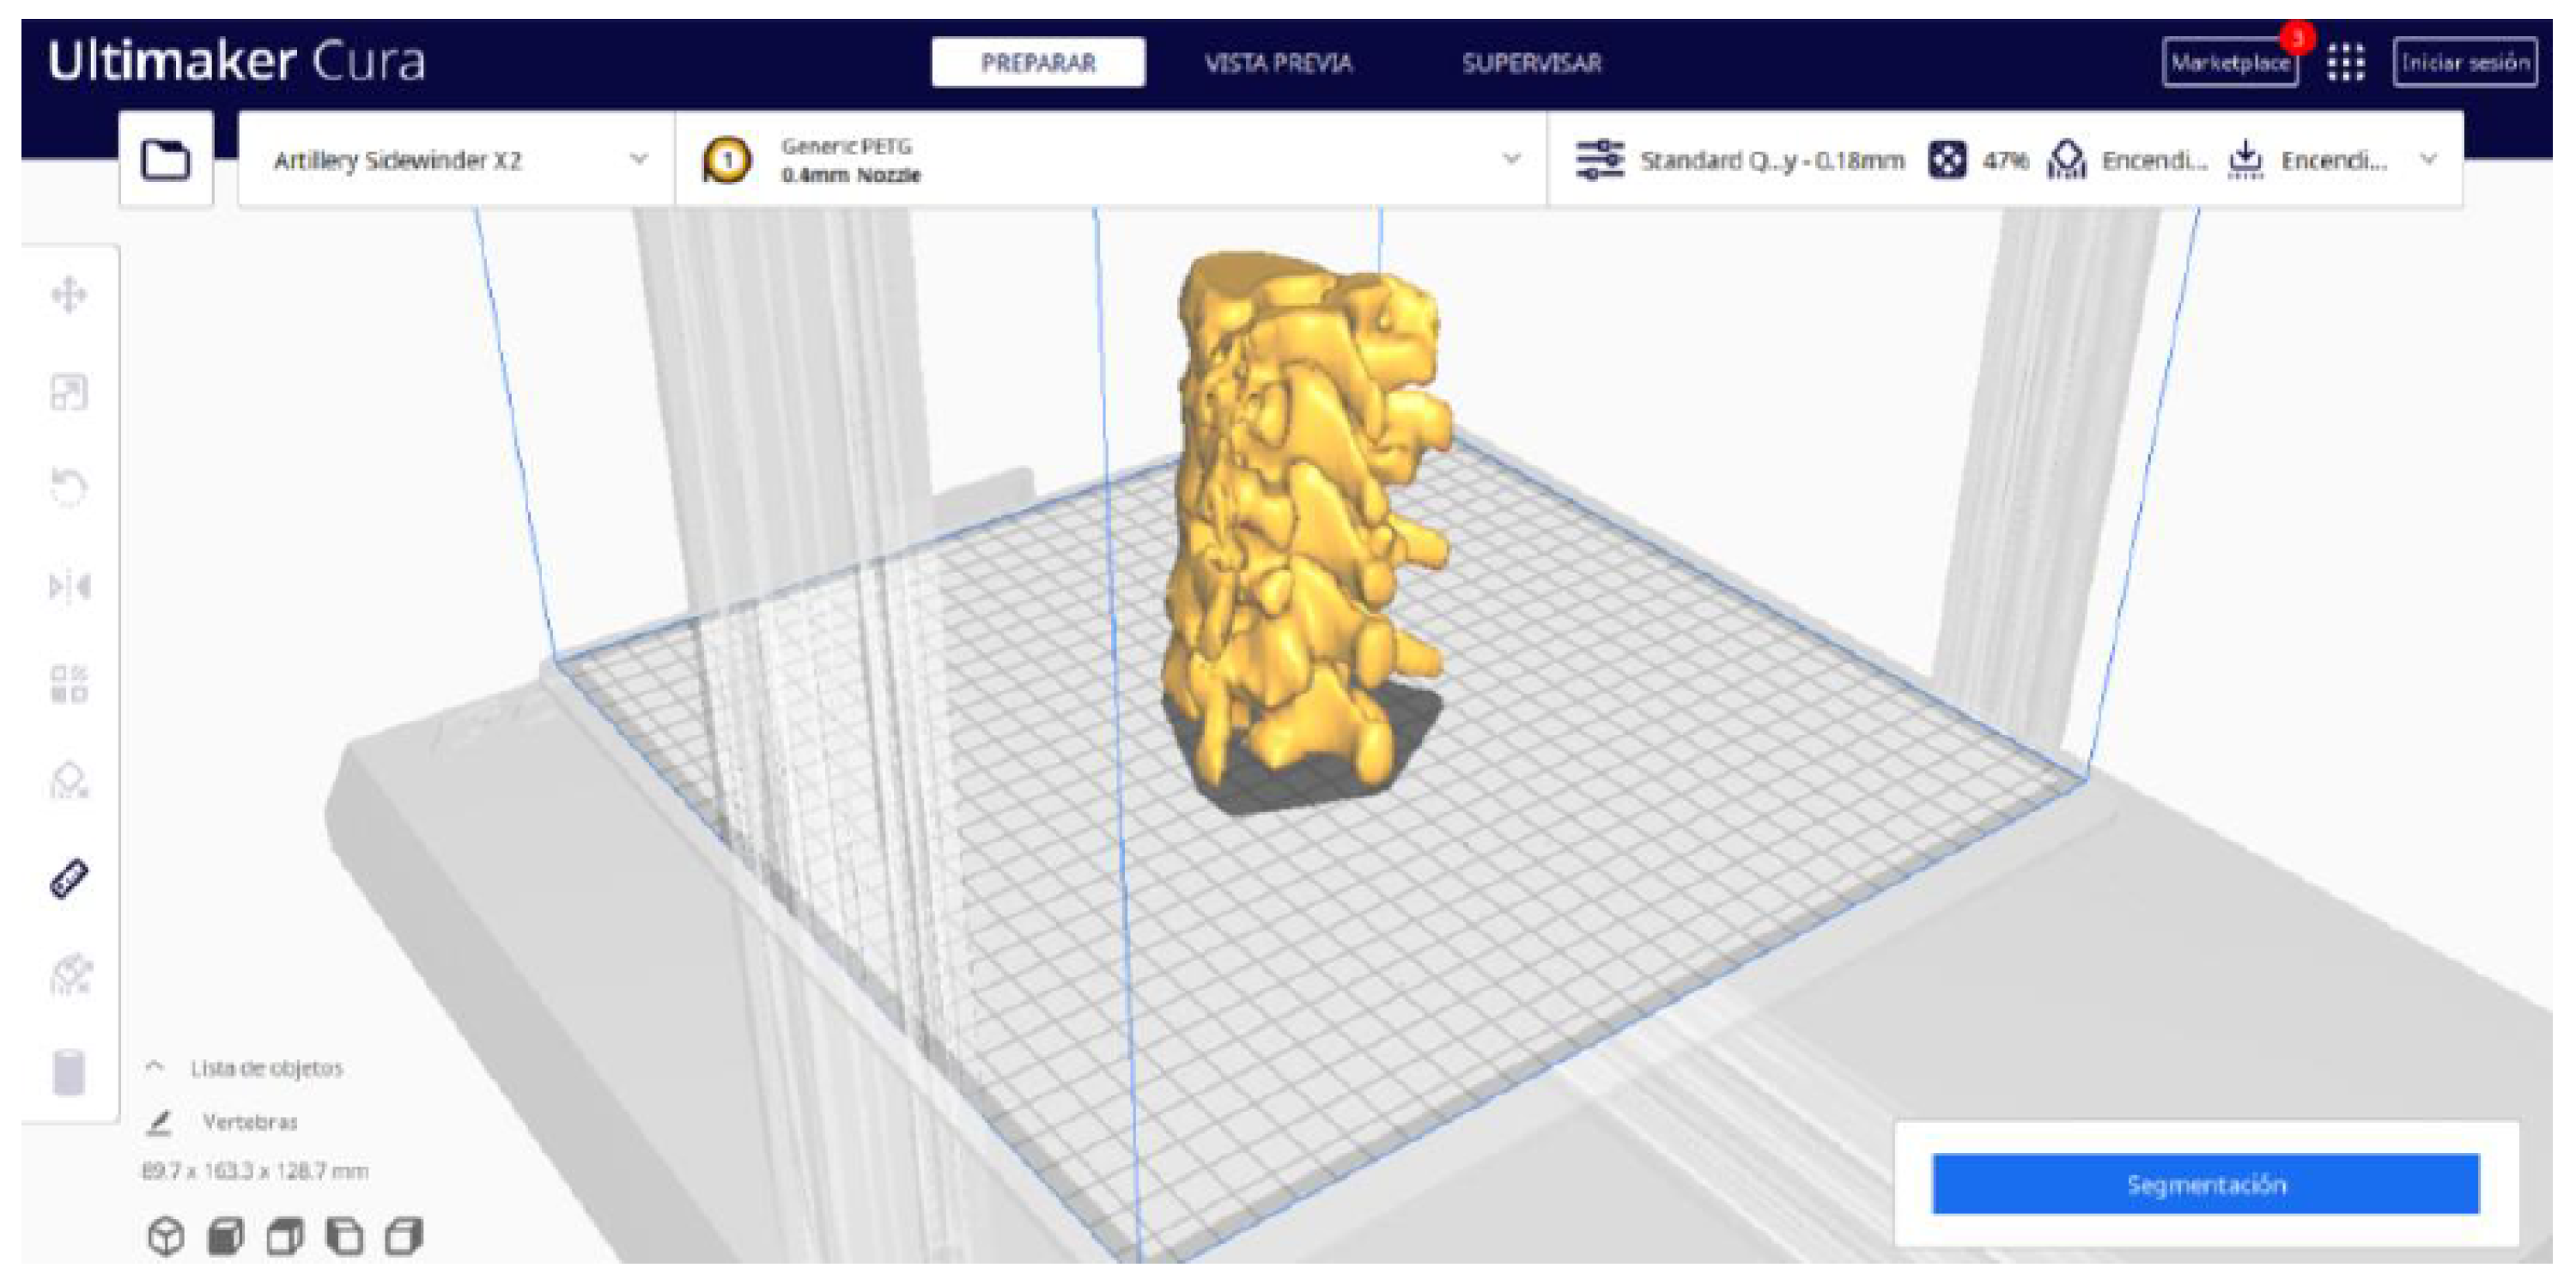

2.2. STL-to-GCODE File Conversion

- Launch the Ultimaker Cura program on your computer.

- Open the STL file you want to print from the “Open File” option in the menu.

- Access the printer settings within Ultimaker Cura.

- Be sure to select the appropriate printer model and material settings for your 3D printer.

- If necessary, make adjustments to the position, scale, or rotation of the model on the build platform within Ultimaker Cura. This allows you to optimise the layout of the model on the printing platform.

- In order to continue the STL file to GCODE conversion process, select the “Segmentation” option in Ultimaker Cura.

- The segmentation tool provides valuable information such as the estimated model weight and estimated printing time, among other crucial data.

3.1.2. STL-to-GCODE File

| Vertebrae | [150, 300] | Median | 0.8 | 0.18 | 25 |

| Vertebrae models | m; m | Artillery Sidewinder X2 |